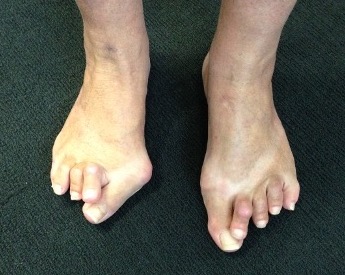

Forefoot

Great toe

Hallux valgus / rigidus

Metatarsalgia

Pathology

Synovitis of MTPJ with capsular destruction

- dorsal subluxation MTPJ

- claw toes develop (MTPJ hyperextended, PIPJ flexed)

- plantar fat pad displaced distally and metatarsal heads exposed to plantar skin

Claw toes